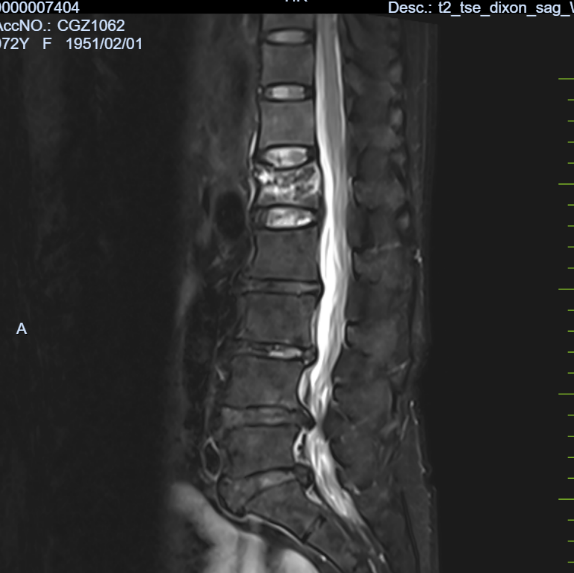

病例三:患者,刘某,女,72岁,因“外伤致腰部及髋部疼痛不适1天”入院。诊断:腰1椎体压缩性骨折,骨质疏松症;行经皮穿刺腰1椎体成形术,手术顺利,术后恢复良好,顺利出院。

腰1椎体压缩性骨 术前X线片 腰1椎体压缩性骨 术前磁共振